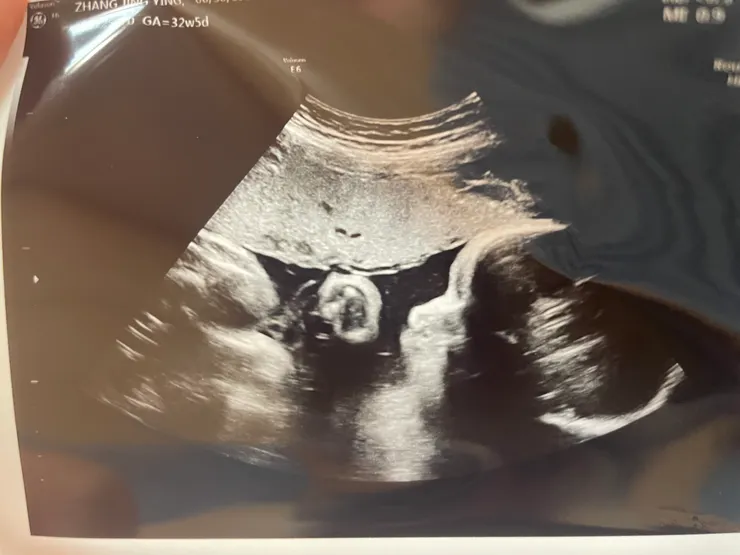

這次超音波檢查細目比較多,也終於是有張較為清晰的側臉照(一向很神秘的寶寶)

Ching的寶寶32週超音波照

3.第三次超音波檢查

(建議32週後執行:評估胎兒心跳、胎兒大小測量、胎位、胎盤位置及羊水量)